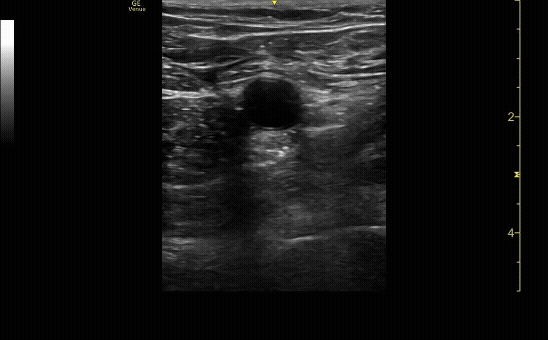

Ultrasound showing compression at the junction of greater sapphenous vein and femoral vein. Femoral artery with pulsatile flow. Be sure to show the vein before and after compression.

c/o Kyle Ackerman, MD